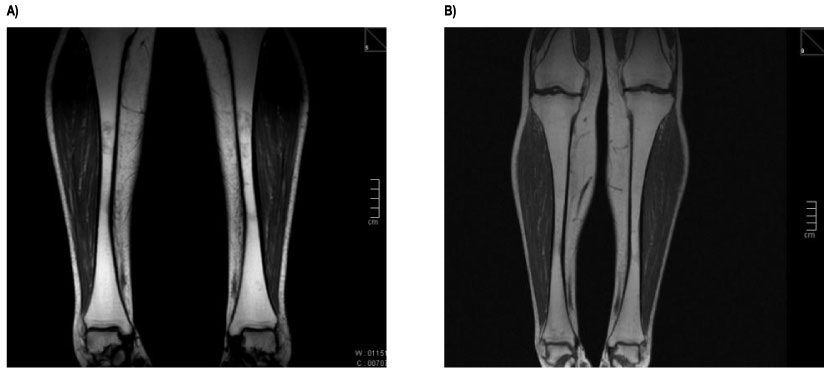

There were clear improvements in the bone components of GD-DS3 such as bone/joint pain and bone marrow infiltration during follow up (Figure 2 and Figure 3). At eliglustat initiation, 3 patients reported moderate or severe bone pain in the previous 30 days, however, at the 6-year follow up these patients reported mild or no/very mild bone or joint pain. Bone marrow infiltration (bone marrow burden [BMB]) was also reduced from marked/severe to moderate in Cases 1 and 2, remained moderate in Case 3 and remained marked/severe in Cases 4 and 5. Prior to eliglustat initiation, Patient 1 had experienced two bone crises in the previous 12 months, whereas no bone crises were reported in any patient following eliglustat initiation.

Figure 2: Coronal T1 - weighted images MR images of tibia of a female Gaucher patient. A) Tibia before switch from imiglucerase to eliglustat. The images obtained detected an abnormal focal changes marrow bone - focal low signal intensity in both diaphysis, sparing the epiphysis and metaphysic; B) After 6y of eliglustat therapy, images of the same patient noted there was increased bone marrow signal in the diaphysis, compared with the baseline, with no lesions detected in diaphysis. View Figure 2